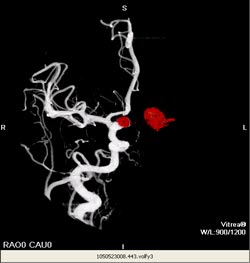

Angiogram: Many large coils in giant skull base aneurysm. Balloons have been detached below the coils to ensure the ICA interior communicating artery is closed.

Courtesy of Dr. Kieran Murphy, Johns Hopkins University, Department of Radiology